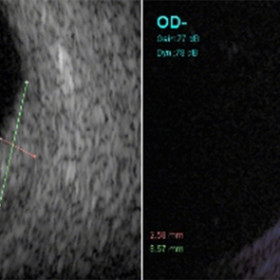

Choroidal hemangioma

Choroidal hemangioma - A-scan reveals high internal reflectivity within the tumor (arrow).